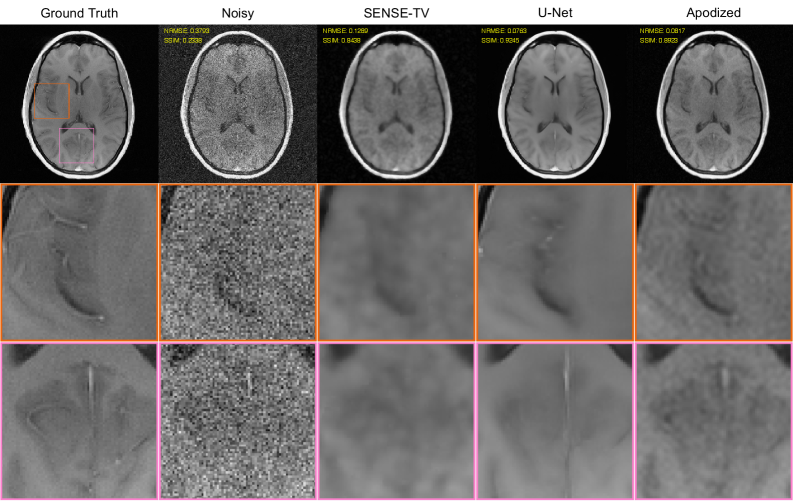

The NRMSE and SSIM values shown in our previous plots can be imperfect measures of image quality and can lack sensitivity to important factors such as spatial resolution and hallucination [kim2018a, antun2020, chan2021]. As a result, it is also important to look closely at the denoising/reconstruction results. Representatitve images are shown for SENSE-TV and U-Net denoising/reconstruction in Figs. 6 and 7, respectively, corresponding to the SNR=2 case. Our subjective assessment of these images suggests that optimizing NN indeed seems to yield meaningful visual improvements in image quality over using the baseline high-resolution acquisition with N=N0N=N_{0}. Specifically, while the denoising/reconstructions in this case have visibly lower-resolution than the ground truth images (as should be expected with NN0N\ll N_{0}), we believe that the resulting images still provide substantially more faithful visual depictions of high-resolution vascular and gray matter structures compared to the images from the high-resolution baseline. On the other hand, while nonuniform averaging produces slightly better NRMSE and SSIM values than uniform averaging, the visual differences between these two approaches are more subtle, and it is difficult to identify a clear winner. This is a common issue in the field, and speaks to the continuing need for better ways of evaluating image denoising/reconstruction performance [kim2018a, chan2021, wang2024, antun2020].

Finally, illustrative results comparing simple linear filtering/apodized reconstruction with optimized acquisition (NN and 𝐰\mathbf{w}) against SENSE-TV and U-Net denoising/reconstruction with the baseline acquisition (unoptimized high-resolution acquisition with uniform-averaging) are shown in Fig. 8. Although the NRMSE and SSIM values in this case suggest that the U-Net offers the best quantitative performance, we personally believe that these metrics are misleading in this case. Instead, we prefer the simple apodized result, which faithfully reproduces many high-resolution vascular and gray matter features that are more difficult to discern in the U-Net and SENSE-TV results. This underscores the importance of designing data acquisition carefully, since even very simple denoising methods with good data acquisition designs can yield major visual advantages over over advanced denoising/reconstruction methods with poorly-chosen data acquisition designs.

Refer to caption

Figure 8: A comparison between advanced denoising reconstruction techniques (SENSE-TV/U-Net) with unoptimized acquisition versus simple linear filtering/apodized reconstruction with optimized acquisition. Results are shown for the SNR=2 case. The left two columns respectively show the ground truth image and the results of simple Fourier reconstruction of the noisy data. The remaining columns respectively show (from left to right): the denoising/reconstruction results obtained with SENSE-TV and the baseline high-resolution uniformly-averaged acquisition, U-Net baseline high-resolution uniformly-averaged acquisition, and apodized reconstruction with optimized nonuniform averaging (i.e., optimized NN and 𝐰\mathbf{w}). This figure otherwise uses the same formatting as Fig. 1 (see the Fig. 1 caption for details).